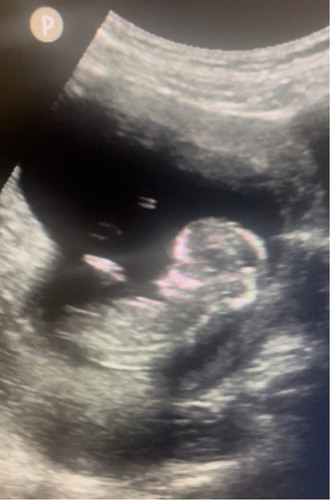

Kindje van mijn beste vriendin 🥰. 12+5 op deze foto. Kunnen jullie hier wat van maken? Ik denk zelf een meisje te zien, maar ik ben geen echte kenner!

Ik zie geen nub hierop

Hoopte al dat jij zou reageren! Volgens de echoscopiste kon je de nub hier niet zien. Zie jij hem wel?